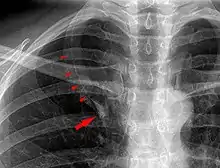

Azygos lobe

In human anatomy, an azygos lobe is a normal anatomical variation of the upper lobe of the right lung.[1] It is seen in 0.3% of the population.[2] Embryologically, it arises from an anomalous lateral course of the azygos vein,[3] in a pleural septum within the apical segment of the right upper lobe or in other words an azygos lobe is formed when the right posterior cardinal vein, one of the precursors of the azygos vein, fails to migrate over the apex of the lung and penetrates it instead, carrying along two pleural layers as the azygous fissure, that invaginates into the upper portion of the right upper lobe.[1]

An azygos lobe is usually an incidental finding on chest x-ray or CT scan, and is not associated with any morbidity.[4][5] However, it can cause technical problems in thoracoscopic procedures.[6]